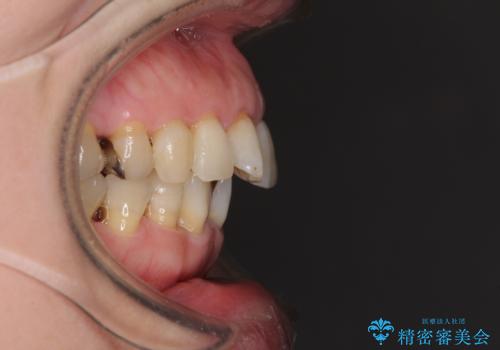

口元の突出感とデコボコが気になっているとのことでしたが、インプラントが既に3本埋入されていたため、抜歯矯正による口元を引っ込めることができない状況でした。

近医での歯周病治療の影響でブラックトライアングルが発現していたため、IPR(歯と歯の間を削る)で隙間を改善しつつ、インプラントを固定源に歯列全体を後方へ移動させることとしました。

インプラントは矯正治療では動かすことができないため、インプラント治療を行う前に矯正治療を行う意思があるのかを確認します。

特に出っ歯などで抜歯矯正となる場合には、インプラントが邪魔になることがあるので注意する必要があります。